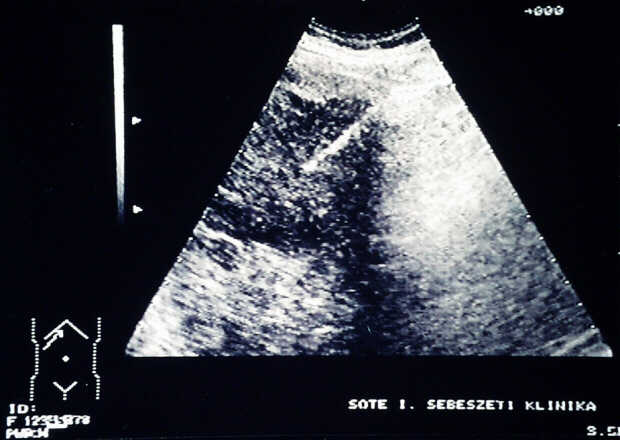

Balazs Járay1, Eszter Székely1, Tamas

Winternitz2, Zsolt Tarján3,

Tibor F. Tihanyi2

12nd

Department of Pathology, 21st Department of Surgery, 3Department

of Radiology, Semmelweis University. Budapest, Hungary